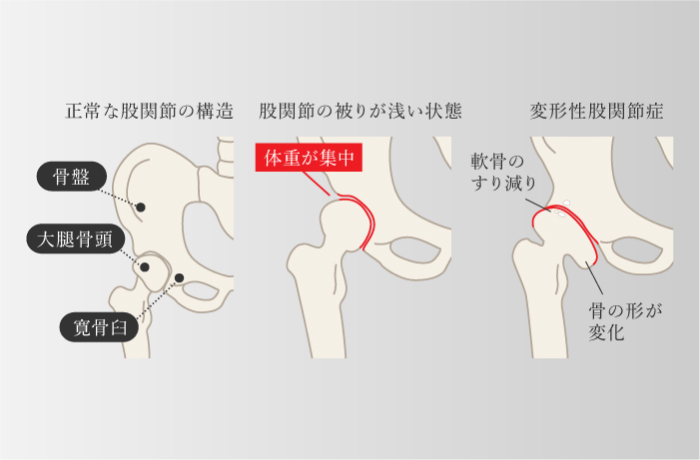

変形性股関節症

股関節に過剰な負担がかかり、軟骨がすり減ることで起こる。 股関節は、受け皿になる寛骨臼と、大腿骨頭がかみ合ってできている球関節で、この大腿骨頭が寛骨臼にしっかりと被さることで体重が支えられている。 大腿骨頭の被り方が先天的に浅い骨格の人は、体重のかかる面が少ないため、加齢とともに股関節に負担が集中し、軟骨のすり減る割合が通常よりも多くなる。